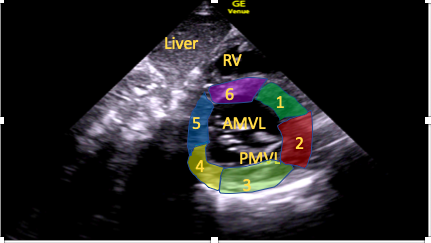

Subcostal Short-Axis Mitral Valve View

Tilting the transducer to point further towards the patient’s cardiac apex will bring the mitral valve leaflets into view (Figure 8).15

Figure 8. Subcostal short-axis mitral valve view.

RV=right ventricle, AMVL=anterior mitral valve leaflet, PMVL=posterior mitral valve leaflet; 1-6 are labelled segments of the LV wall: 1=anteroseptal, 2=anterior, 3=anterolateral, 4=inferolateral, 5=inferior, 6=inferoseptal